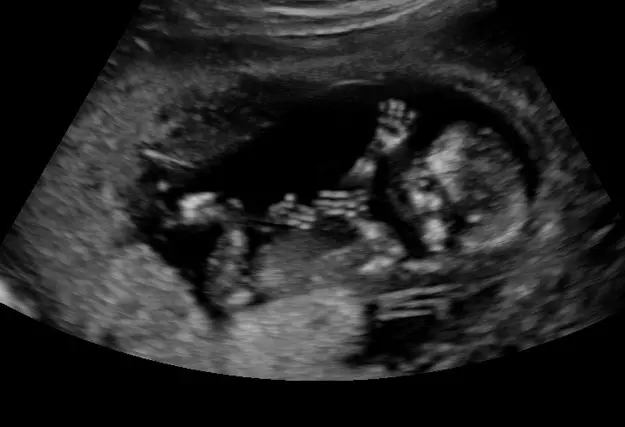

Twenty-five-year-old Courtney breathed those words as she gazed at the ultrasound screen at the pregnancy center at which I work.

The young mother, the sonographer, and I stared in awe at the image of the bouncy 14-week-old baby in the womb.

“Look at those hands! I can see the fingers! And look at those long legs! It’s gotten big!” Courtney said.

Therefore, Courtney scheduled a second ultrasound with us, and her excitement at seeing her developing child spilled forth.

I saw her smiles and heard her comments during that second ultrasound. I silently celebrated as I watched the lively baby.

Along with Courtney and the nurse, I witnessed the developing spinal cord, saw the beating heart, and observed the baby’s antics.